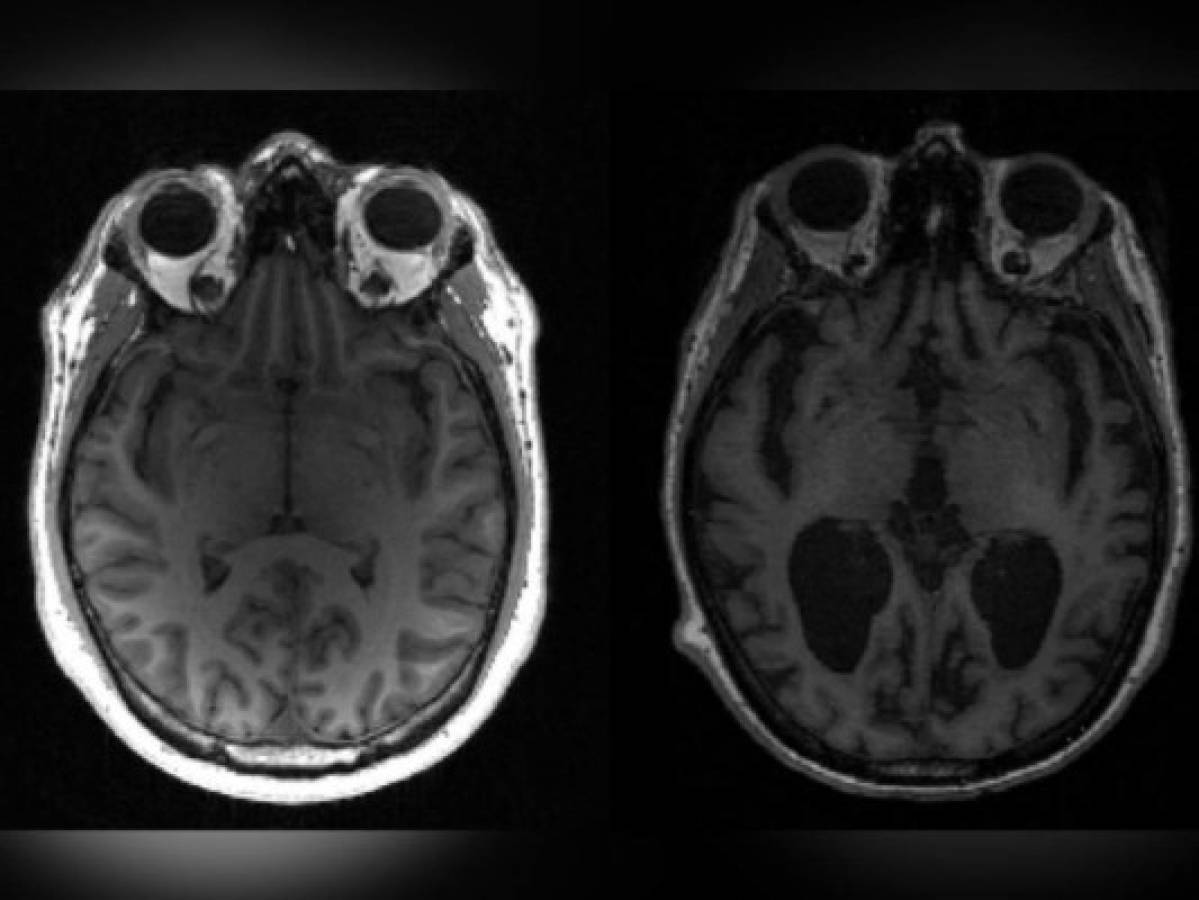

La esclerosis múltiple es una enfermedad autoinmune del sistema nervioso central (cerebro y médula espinal). Provoca un disfuncionamiento del sistema inmunitario, que ataca a la mielina, que protege las fibras nerviosas.

Evolucionando por etapas, la enfermedad es muy variable de un paciente a otro, pero puede conllevar secuelas, y es causa frecuente de discapacidad entre jóvenes adultos.